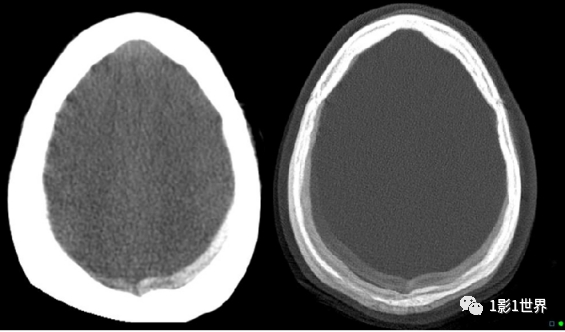

类似硬膜下血肿的运动伪影